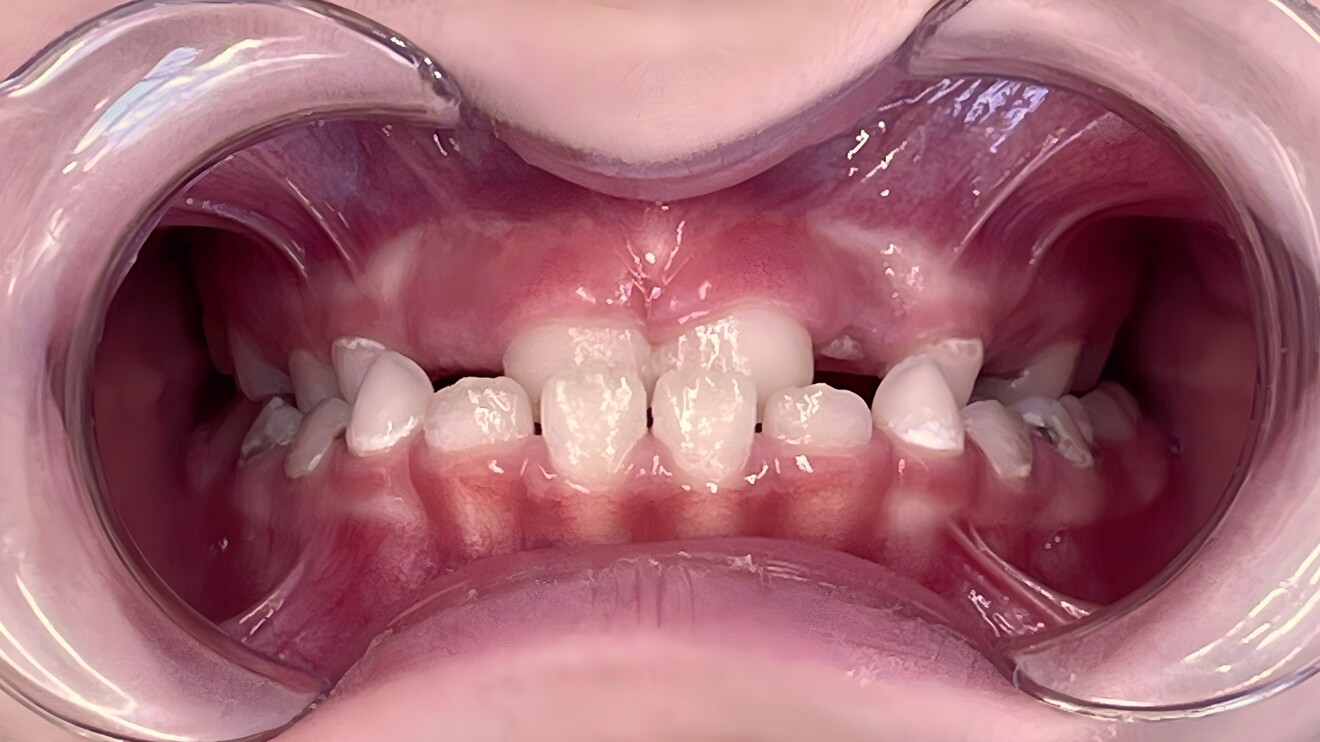

Figs. 1d–h: Pre-treatment records. Intra-oral photographs.

Fig. 1e

Fig. 1f

Fig. 1g

Fig. 1h